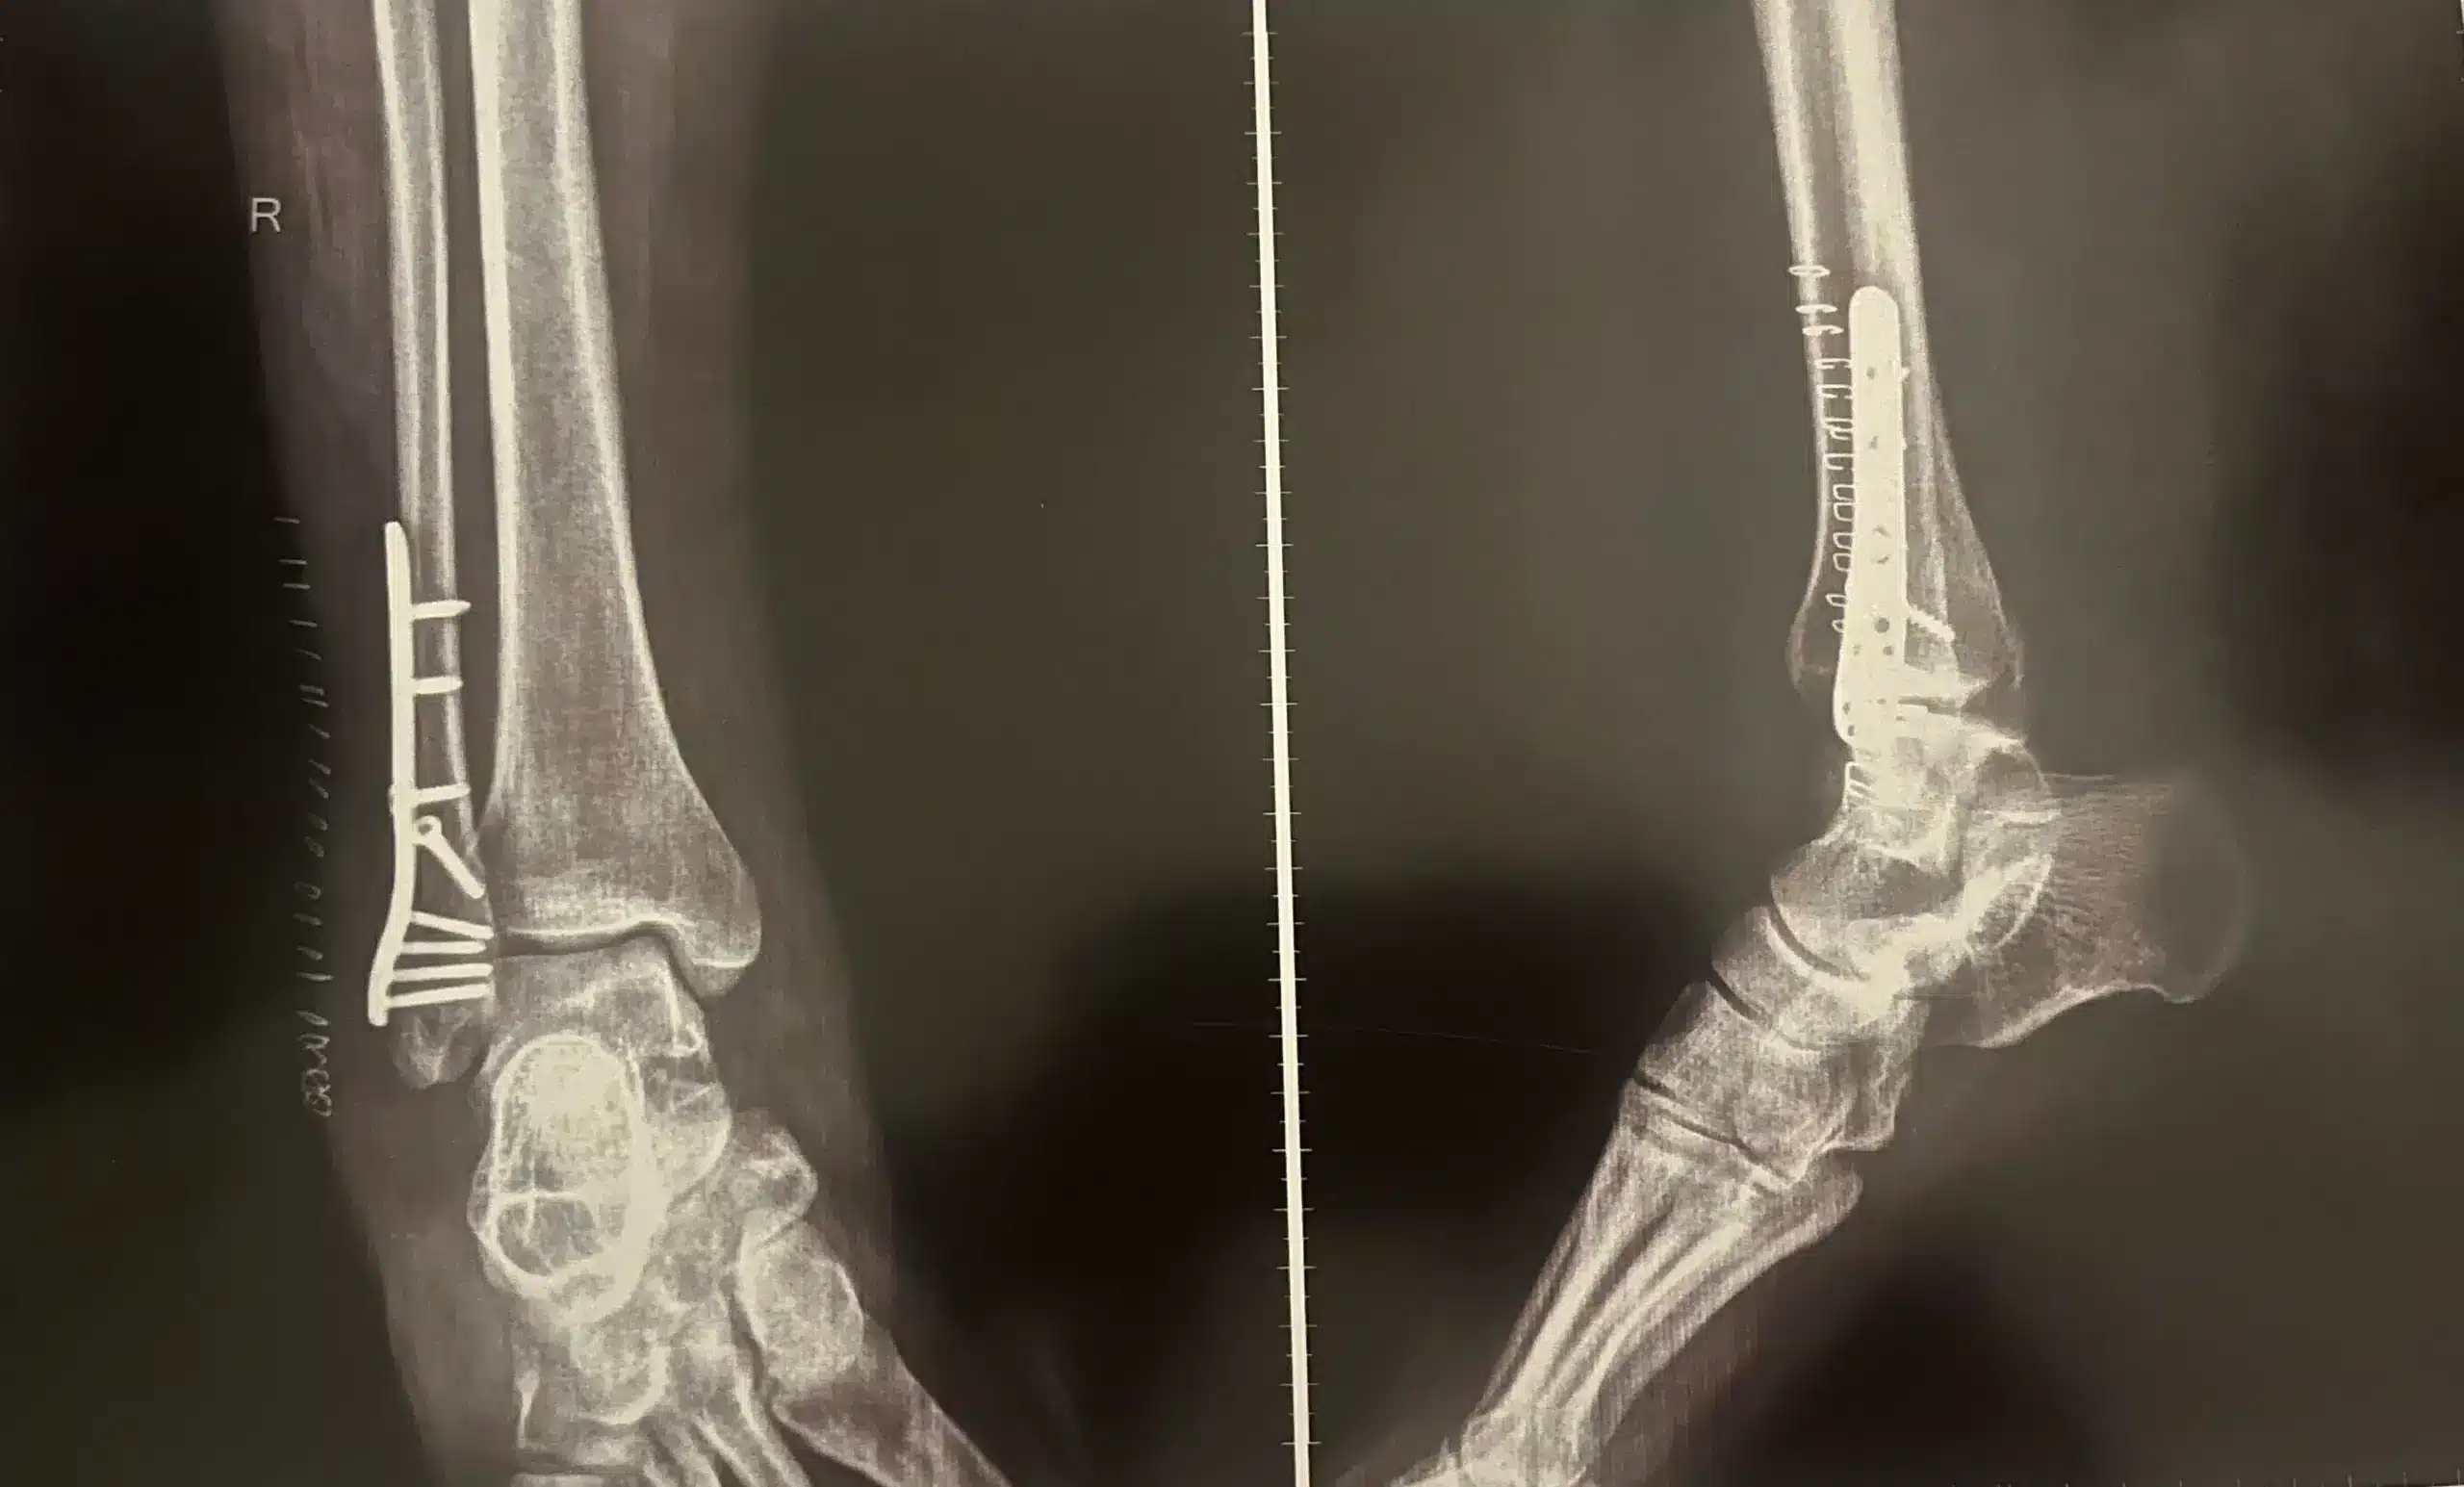

عمليات الشرائح والمسامير، من المعروف أن كل الأشخاص معرضون للكسر في أي وقت ففي الحالات البسيطة يتم علاجها بالجبيرة، ولكن في الحالات المعقدة منها تحتاج إلى تركيب الشرائح والمسامير من أجل ضمان ثباتها والتئامها بالشكل الصحيح.

المريض الذي يتعرض لكسور بالغة ويخضع لعملية جراحية من أجل تركيب الشرائح والمسامير يتمكن من استعادة نشاطه وحركاته اليومية بشكل طبيعي ودون أن يعاني من الألم.

حيث تساعد الشرائح والمسامير على التئام حالات الكسر بطريقة طبيعية واستقرار العظام في أماكنها الصحيحة ويقوم جسم المصاب بتقبل وجودها حيث لا يتعامل معها على أنها جسم غريب.

حدوث الكثير من حالات الكسر متعددة الشظايا في العظام، حيث يتم إجراء الجراحة لإزالة القطع العظمية المتكسرة وتنظيف مكان الإصابة.

عندما يكون الكسر قريبًا من أحد المفاصل، قد يتسبب ذلك في تلف المفصل أو الأنسجة المحيطة به.